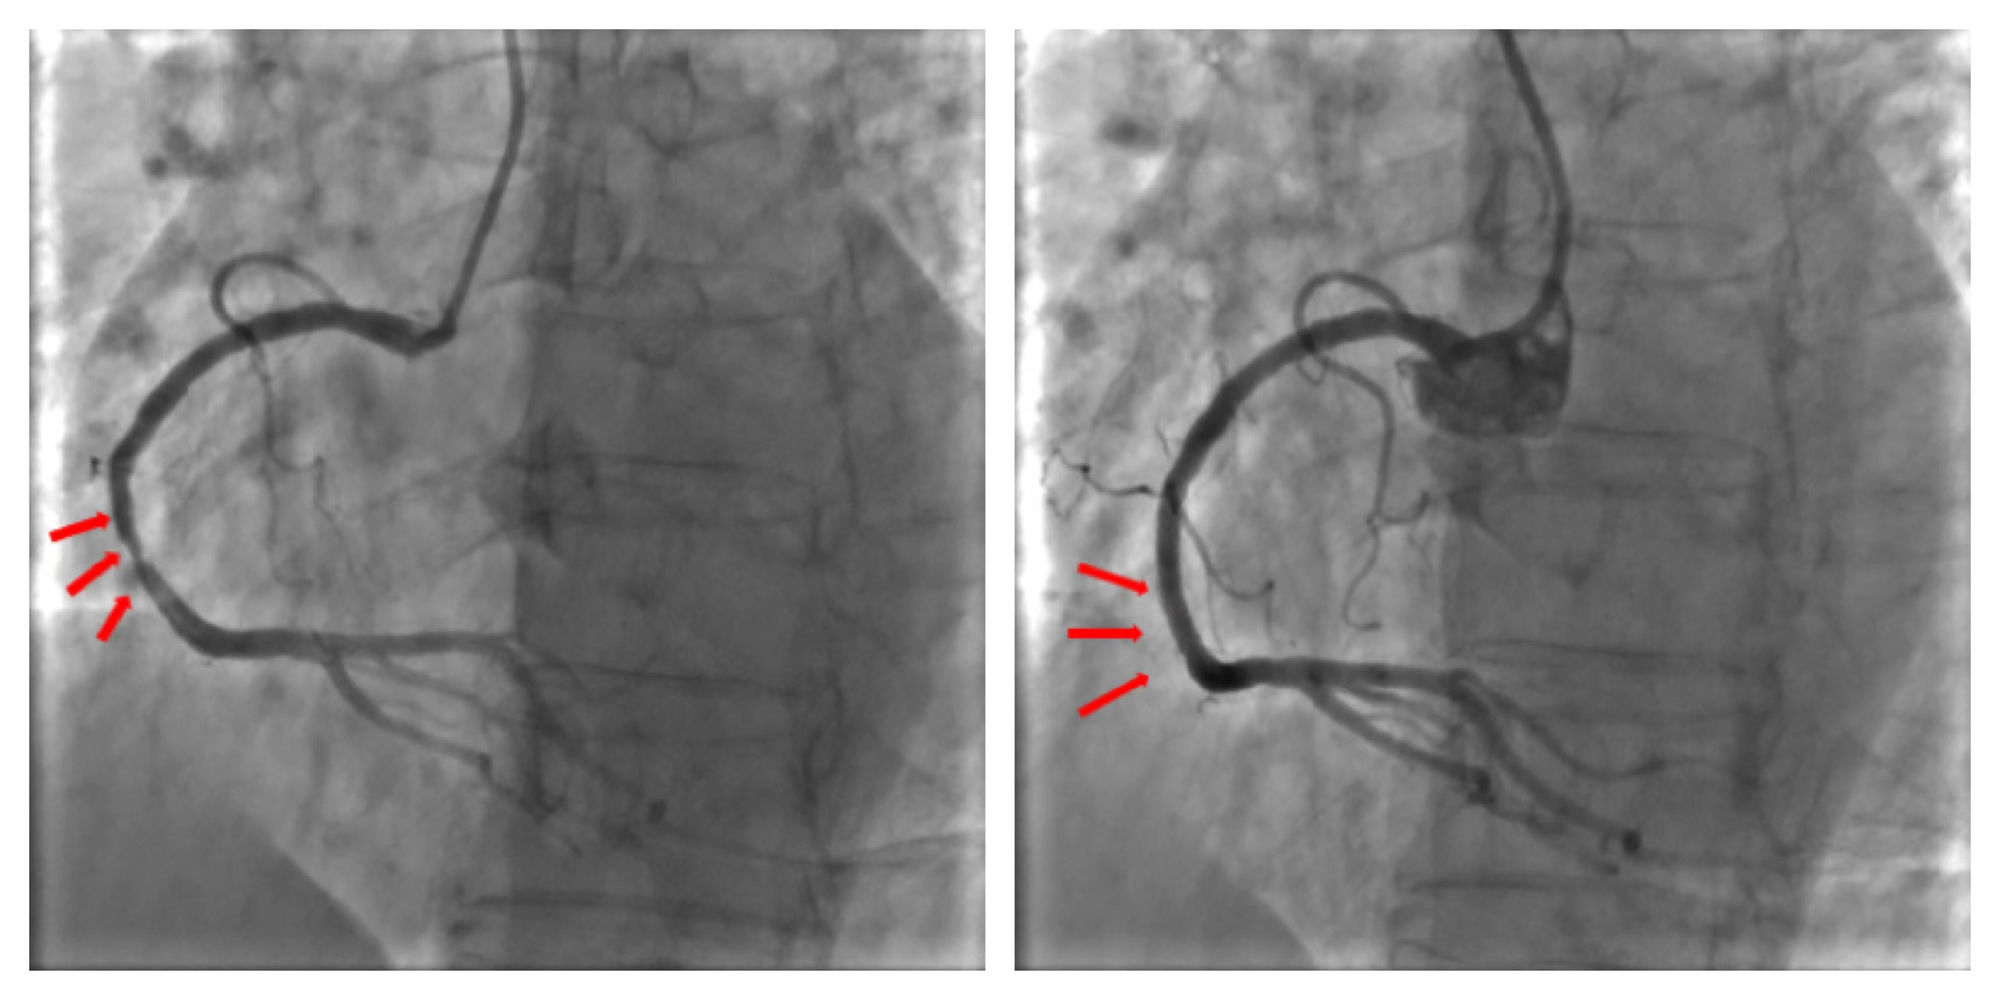

IBS?冠脉支架中国确证性临床钻研的首例受试者入组由俞梦越教授率其团队顺利发展。术中冠脉造影提醒:单支血管病变,右冠中段狭幼80%,在光学有关断层成像(OCT)领导下,成功实现靶血管的血运沉建,右冠中段植入1枚支架,术中无任何并发症产生,达到预期医治成效,患者术后性命体征安稳。